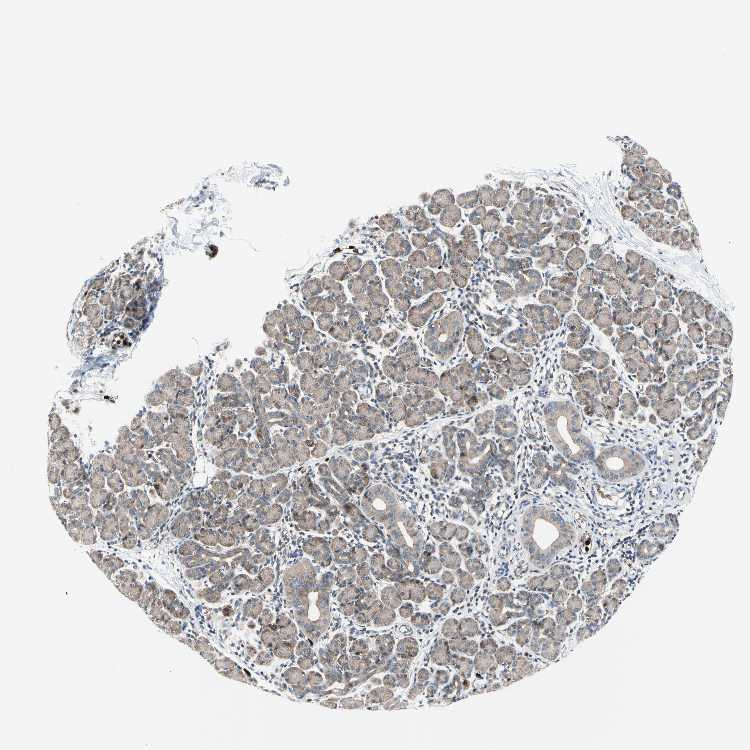

SALIVARY GLAND - Antibody stainingi

Antibody staining in the annotated cell types in the current human tissue is reported as not detected, low, medium, or high, based on conventional immunohistochemistry profiling in selected tissues. This score is based on the combination of the staining intensity and fraction of stained cells.

Each image is clickable and will lead to virtual microscopy that enables deeper exploration of all samples and also displays staining intensity scores, fraction scores and subcellular localization as well as patient and tissue information for each sample.

Antibody CAB011618Antibody CAB070164

Glandular cells MediumMedium